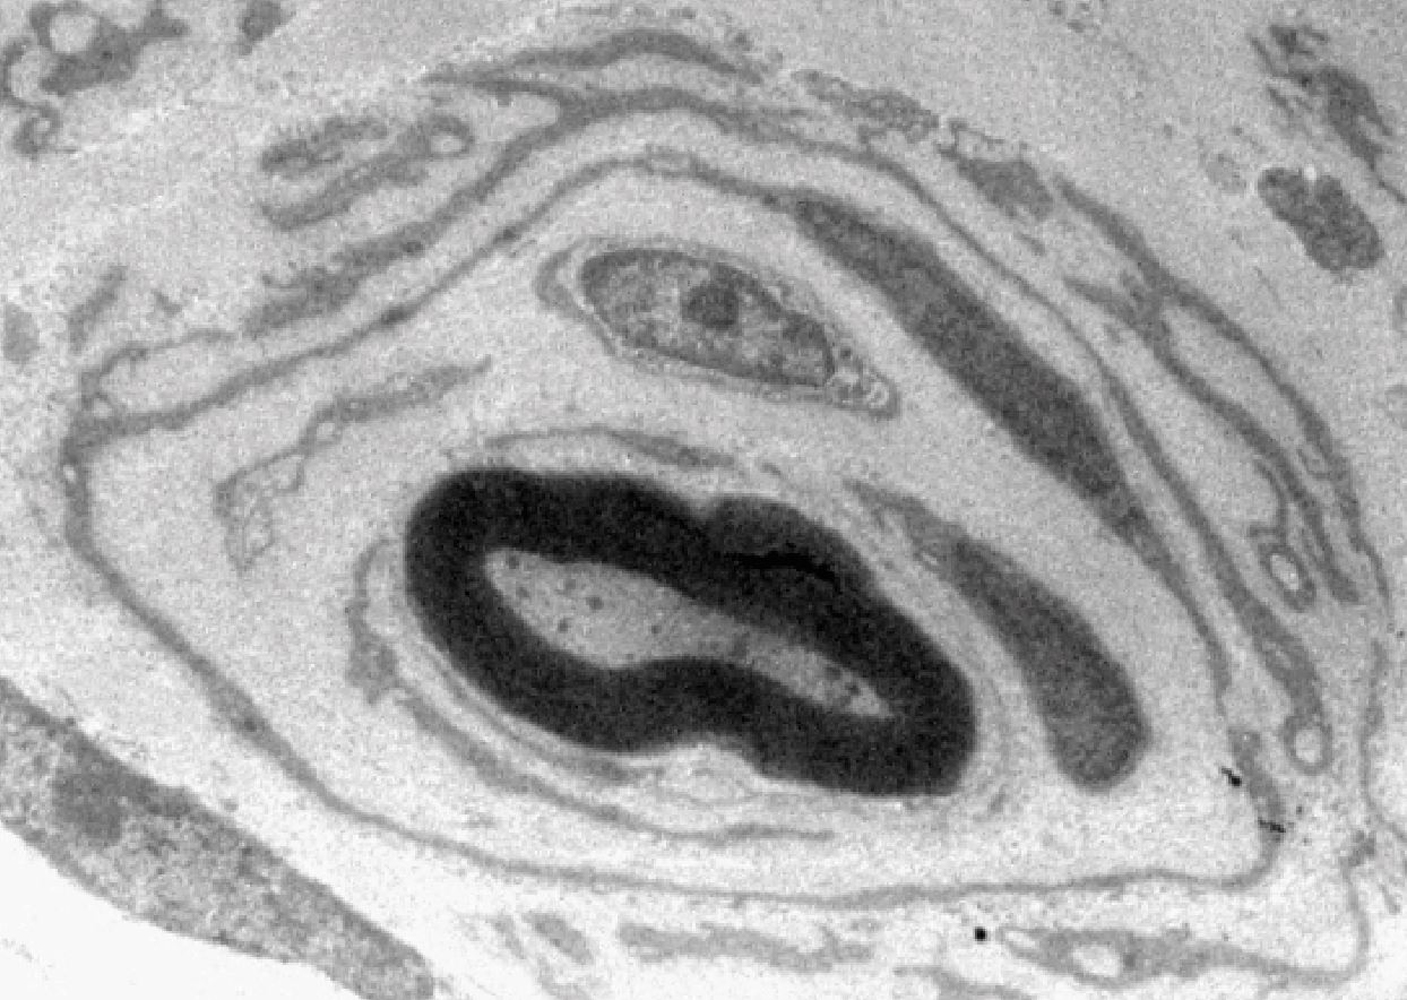

Unser Körper ist von Millionen Nervenfasern durchzogen, die Strom leiten wie Kabel. So können beispielsweise Muskeln angesteuert oder Sinneseindrücke weitergeleitet werden. Wie Kabel sind die Nervenfasern elektrisch isoliert: Durch spezialisierte Zellen, den Schwann-Zellen, die sie mit einer fettreichen Scheide, dem Myelin, ummanteln. Dadurch können Signale besonders schnell weitergeleitet werden. Bei Menschen, die an der häufigsten vererblichen Neuropathie, der CMT1A Erkrankung, leiden, ist die Interaktion zwischen Nervenfasern und Schwann-Zellen gestört. Nerven betroffener Patienten weisen im Querschnitt viele Fasern mit zahlreichen fehlerhaft angelagerten Schwann-Zellen auf. Dieses als „Zwiebelschalenformation“ bezeichnete Phänomen ist schon seit über 100 Jahren bekannt und dient Ärzten seither als wichtiges Diagnosekriterium. Ihre Entstehung ist aber komplett unverstanden.

Die Leipziger Forscher konnten nun herausfinden, dass Zwiebelschalenformationen Ausdruck eines aus dem Ruder gelaufenen Reparaturversuchs sind. „Das periphere Nervensystem hat die Fähigkeit, sich nach einer akuten Nervenschädigung, wie zum Beispiel einer Quetschung oder Schnittverletzung, selbst zu reparieren. Dabei ordnen sich die Schwann-Zellen hintereinander der Reihe nach an und bilden so ein langes Band, entlang dessen die Nervenfasern erneut auswachsen. Während dieser Zeit produzieren Schwann-Zellen den Wachstumsfaktor Neuregulin-1, ein zeitlich begrenztes Signal, das die Reparatur verletzter Nerven unterstützt“, erklärt Dr. Ruth Stassart von der Abteilung für Neuropathologie am Universitätsklinikum Leipzig, Seniorautorin der Studie. „In der CMT1A Erkrankung kommt es hingegen zu einer dauerhaften Produktion des Neuregulin-1 Signals in erkrankten Schwann-Zellen. Dies führt dazu, dass die Schwann-Zellen zahlreiche Reparaturbänder bilden, die jedoch in dieser Menge überhaupt nicht benötigt werden. So entstehen schlussendlich die zahlreichen Zwiebelschalenformationen, die wir in Nervenbiopsien von Patienten nachweisen können“, so die Wissenschaftlerin weiter.